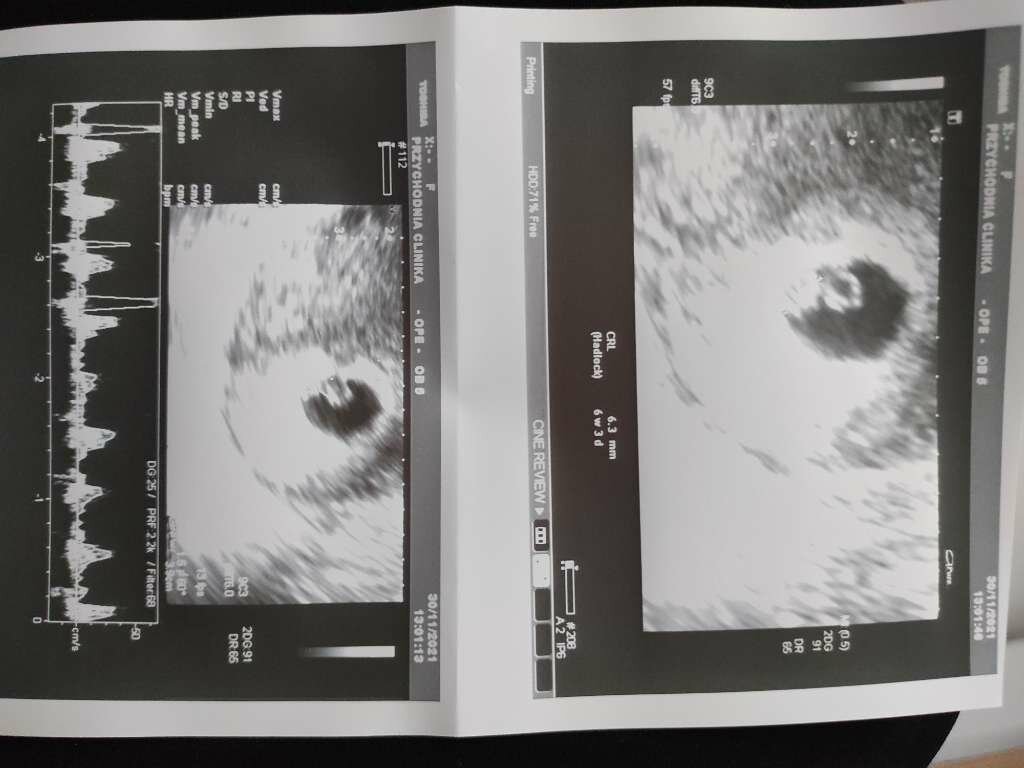

Jesteśmy już oo wizycie.

❤️ bije

Dostałam dalej duphaston plus dodatkowo luteine dopochwową. Jesli chodzi o śluz to norma ponoć.

Załączniki

• 6a2a59a2-cce8-4a1e-bff1-07fb925647e9.jpg